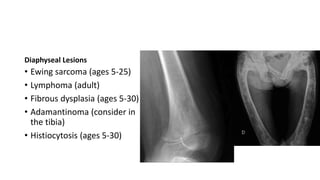

Diaphyseal Lesions

• Ewing sarcoma (ages 5-25)

• Lymphoma (adult)

• Fibrous dysplasia (ages 5-30)

• Adamantinoma (consider in

the tibia)

• Histiocytosis (ages 5-30)